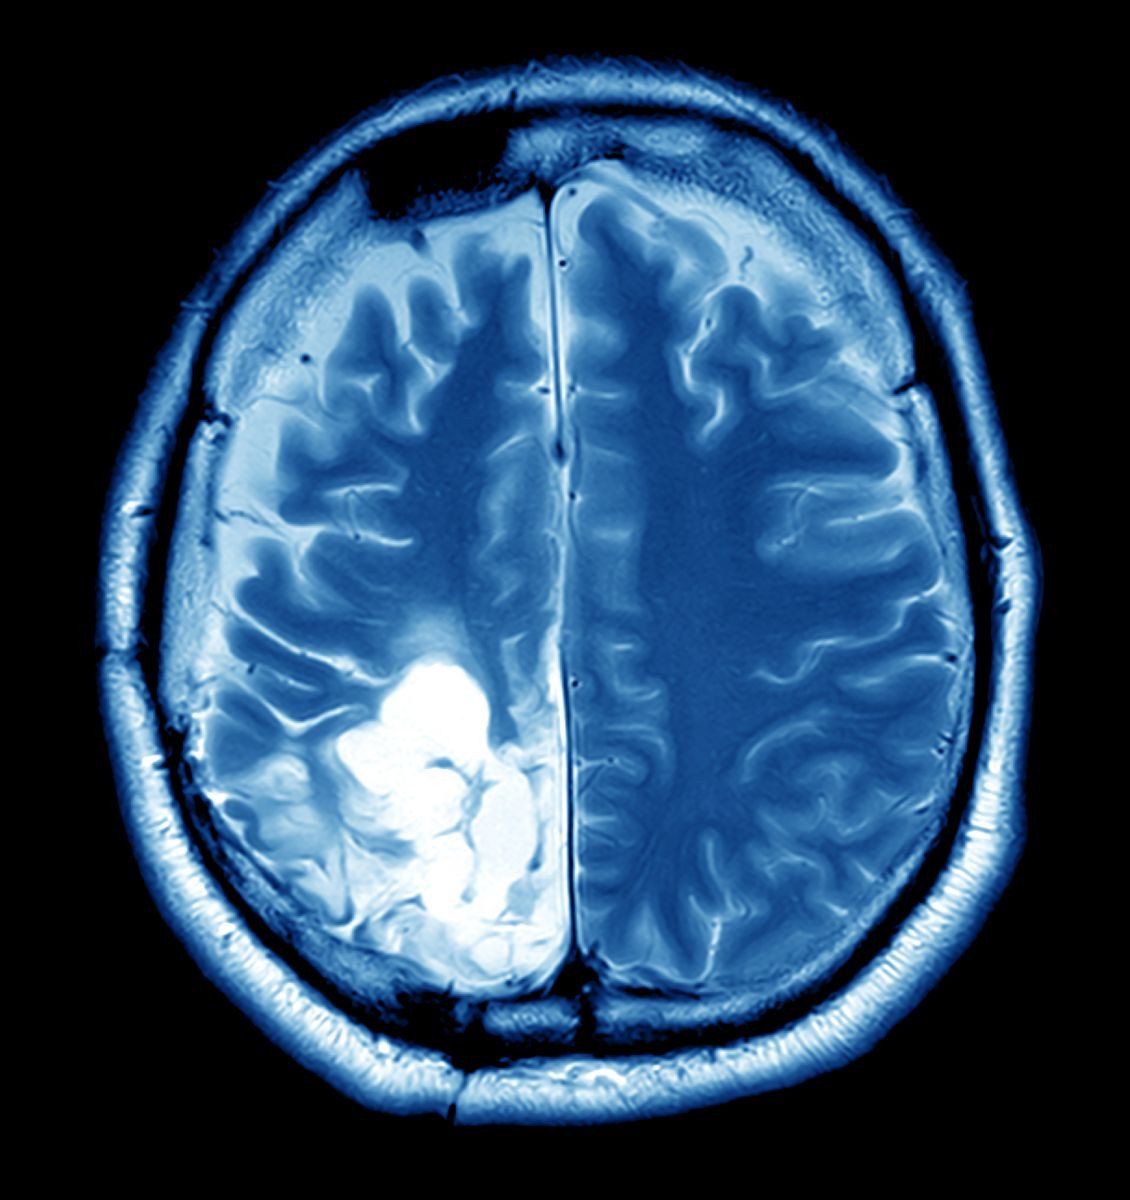

In Aditi's case, the decision to undergo brain tumor surgery was life-changing. The procedure was meticulously planned by a team of specialists who used advanced imaging technologies to map out the exact location and size of the tumor. This precision minimized risks and ensured the best possible outcome.

The surgery was a success, and the transformation in Aditi's life was nothing short of miraculous. Post-surgery, she was no longer plagued by debilitating headaches or vision problems. More importantly, she was able to return to her passions with renewed vigor. This story is not just Aditi’s—it resonates with countless others who have found a new lease on life through the skilled hands of dedicated neurosurgeons.